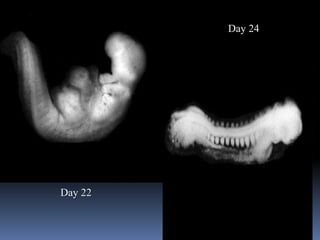

Day 22

Day 24